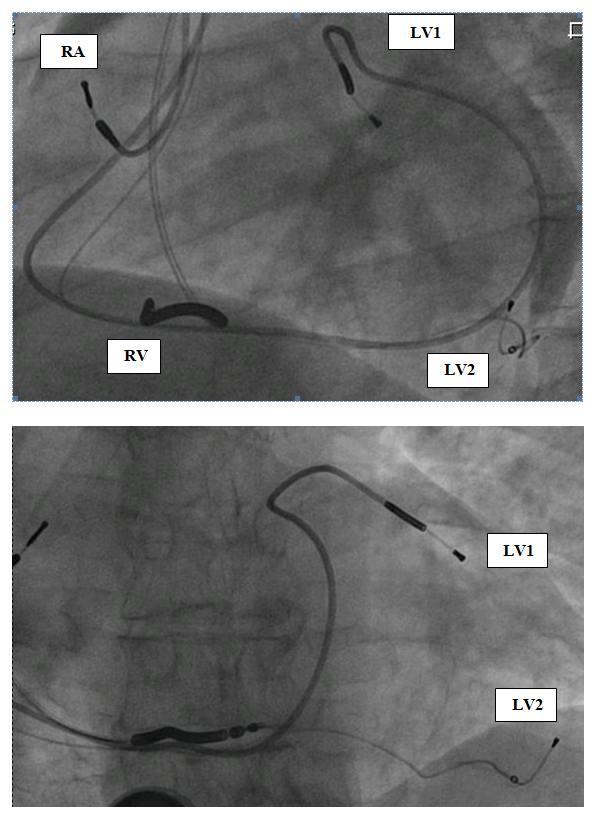

He was treated with maximal tolerated doses of sotalol, quinidine and then was fully loaded with amiodarone (each antiarrhytmic drug at a time) along with beta blockers. Despite those antiarrhythmic drugs (several months each), the patient had recurrent hospitalizations for HF exacerbations and SMVT episodes. The patient had an indication for ICD implantation for secondary prevention and although the patient had narrow QRS, we decided to implant a CRT-D because we anticipated a need for overdrive RV pacing in a patient with an upfront severe LV dysfunction and an expected further LV function deterioration. Furthermore, the final decision was to implant two LV leads at different locations, aiming for a stronger possible antiarrhythmic effect – as proposed in the discussion section. The patient gave his written informed consent to the procedure. A transvenous biventricular ICD (PROTECTA, Model D364TRG, Medtronic Inc., Minneapolis, MN, USA) was implanted and was connected to one right atrial (RA) lead, one right ventricular (RV) lead and two left ventricular (LV) leads. RV lead (bipolar, active fixation, Model 6947-65cm, Medtronic Inc.) was positioned through a left cephalic approach in the RV apex; the other leads were inserted through left subclavian approach. RA lead (bipolar, passive fixation, Model 5592-53cm, Medtronic Inc.) was positioned in the appendage. One LV lead (bipolar, Model 4194-88cm, Medtronic Inc.) was positioned in an anterior branch of the coronary sinus system (Figure 1, LV1). The second LV lead (bipolar lead, Model 1258T, St. Jude Medical Inc., St. Paul, MN, USA) was positioned in a posterior branch of the coronary sinus system (Figure 1, LV2). The two LV leads were connected through a bipolar Y-connector (thus, every biventricular pacing (BVP) was a multisite BVP). The device was programmed with a short atrioventricular interval to assure BVP. LV pacing was simultaneous in the two LV leads (through a Y-connector). LV-RV VV interval could be programmed but was set to LV preceding RV in 10 msec (the interval that showed the thinnest QRS complex). Immediately post-implantation of LV leads and before connecting the leads to the device the PVCs still existed – ruling out the possibility of traumatic injury of the VT focus during implantation as a possible mechanism of VT abolishment. After connecting the leads to the device it was programmed to multisite biventricular pacing with a lower rate of 80. 24-hour Holter monitoring one day post-implantation showed 0.1% VPBs (116/24 hours) with no VT episodes (Figure 2). In order to evaluate the role of overdrive pacing or long-short cycle prevention in the antiarrhythmic effect, a day later the device was programmed AAI with a lower rate of 85 bpm. A consecutive 24-h Holter monitoring showed 7.3% PVCs (9141/24 hours) and no VT episodes. The device was then programmed BVP at a lower rate of DDD-50 (to prevent overdrive pacing). Further 24h-Holter monitoring showed 1% of PVCs (1169/24 hours), with no VT episodes (Figure 2). Periodic follow-up in the ICD clinic showed no more VT episodes since implantation. Antiarrhythmic drugs were discontinued later on, and the patient was never admitted for hospitalization. There were no changes in his medications (ACE-I and Carvedilol 25 mg BID), though his diuretics were reduced over time. HF symptoms were improved dramatically, with NYHA functional class II. Echocardiography one year post-implantation showed major improvement: LVEF 33% and LVESV/LVEDV of 71/107 ml. The BVP was turned off after a year of arrhythmic, clinical and echocardiographic improvement. A consecutive 24-h Holter monitoring showed 8% PVCs (9915/24 hours) and 9 VT episodes (Figure 2). The patient felt weakness, dizziness and shortness of breath. All complaints had resolved after turning the BVP on again. A follow-up echocardiography one year later showed EF of 45%.

Figure 1: Fluoroscopy LAO and AP views showing the four leads. LV1: Left Ventricular Lead Positioned in Anterior Branch of Coronary Sinus; LV2: Left Ventricular Lead Positioned in Posterior Vein; RA: Right Atrial Leads; RV: Right Ventricular Lead.